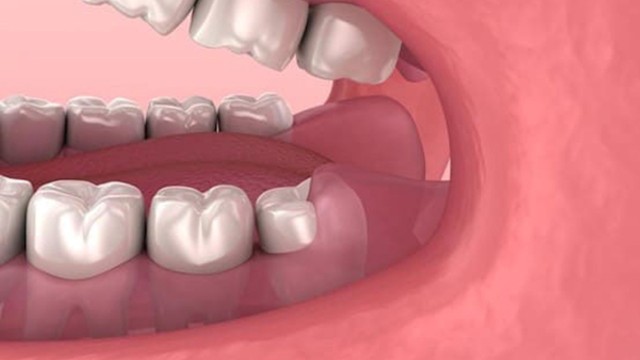

:format(webp)/rang_khon_moc_lech_khong_nho_co_sao_khong_1_fc350503d2.png)

Răng khôn mọc lệch là một trong những vấn đề phổ biến gây ra nhiều phiền toái cho sức khỏe răng miệng. Việc nhổ răng mang lại nhiều bất tiện như đau đớn, tốn nhiều chi phí cùng công sức và thời gian, do đó nhiều người hay đặt ra câu hỏi rằng răng khôn mọc lệch không nhổ có sao không. Hãy cùng tìm hiểu thông qua bài viết dưới đây.